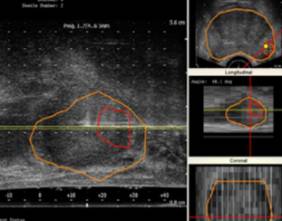

Esta nueva técnica, que requiere de una tecnología específica, combina en tiempo real la resonancia magnética de próstata multiparamétrica (RMmp) con la ecografía, de forma que se obtienen para biopsia los tejidos realmente sospechosos de corresponder a tumores clínicamente significativos que sin tratamiento pueden comprometer el pronóstico vital del paciente y son subsidiarios de intervención.

"La resonancia magnética de próstata multiparamétrica combina diferentes secuencias anatómicas y funcionales permitiendo identificar por imagen aquellas zonas con riesgo elevado de ser tumores con significación clínica", explica el doctor Miguel Sánchez Encinas, jefe del Servicio de Urología del HURJC.

"Fusionando en tiempo real las imágenes de este tipo de resonancia, se consigue aumentar la precisión diagnóstica llegando a una sensibilidad del 92%, superior a la obtenida con ecografía convencional y que obtenemos mientras el paciente está en el quirófano. Además nos permite una precisión diagnóstica mucho más elevada dado que se puede descartar la presencia de tumores prostáticos significantes casi con el 100% de seguridad, lo que sitúa al HURJC a la altura de los más prestigiosos centros internacionales que trabajan en este campo", añade el especialista.

En este contexto la técnica combinada de RMmp y ecografía, que permite al especialista estudiar a la vez diferentes secuencias anatómicas y funcionales, surge como una nueva herramienta para identificar los tejidos de la próstata que conllevan un riesgo elevado de ser tumores con significación clínica con potencial letal para el paciente.